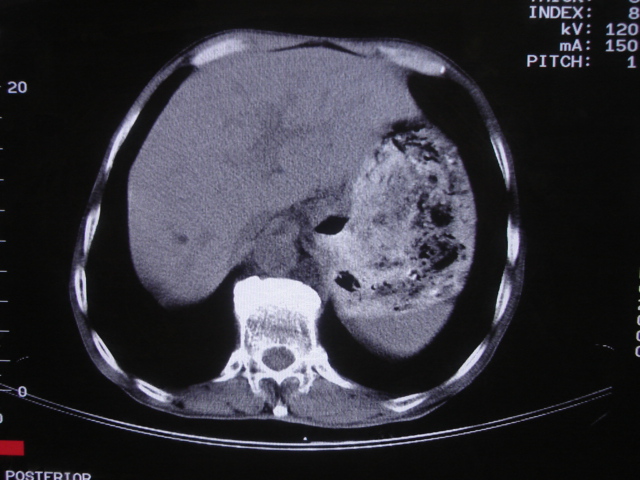

以下是引用深泽交通医院在2008-7-17 12:39:00的发言:[br]胃下垂;胃窦占位